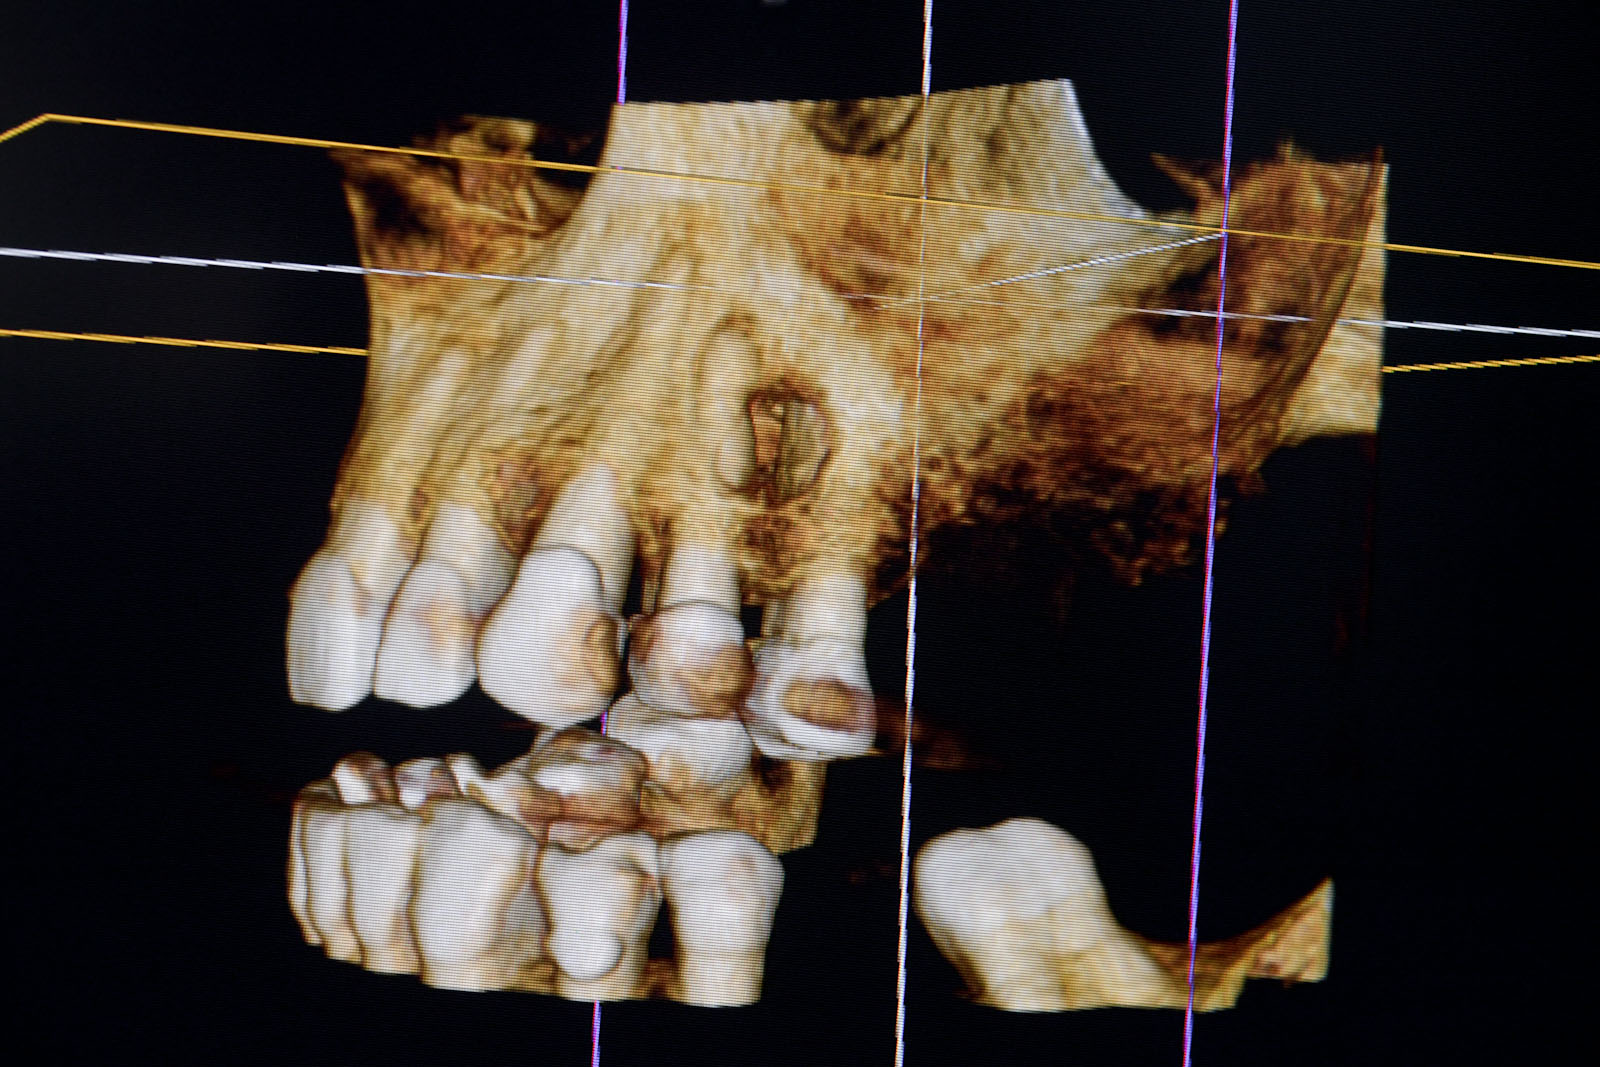

- Istnieje możliwość precyzyjnego wirtualnego planowania pozycji implantu jarzmowego w kościach szczęk jeszcze przed samym zabiegiem operacyjnym. Odbywa się ono na ekranie komputera w trójwymiarowym obrazie, generowanym dzięki cyfrowym danym z tomografii stożkowej CBCT oraz oryginalnej aplikacji NobelClinitian. Ta szczególna forma diagnostyki poprawia precyzję i skraca czas chirurgicznej procedury implantacji.

Tomografia komputerowa stożkowa CBCT – ocenia wszystkie powyższe parametry anatomiczne, które przedstawia na trójwymiarowym obrazie.

Wirtualne planowanie zabiegu w aplikacji NobelClinician na podstawie danych z CBCT.

CBCT, które wybiórczo może okazać stan kości w pozostałej części zębodołowej szczęk, stan oraz powietrzność zatok szczękowych, co jest istotnym parametrem kwalifikującym pacjenta do zabiegu operacyjnego, stan przegrody nosa